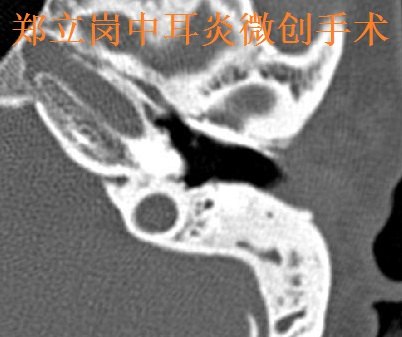

郑立岗中耳乳突炎耳内镜微创+咽鼓管球囊扩张

402x337 - 27KB - JPEG